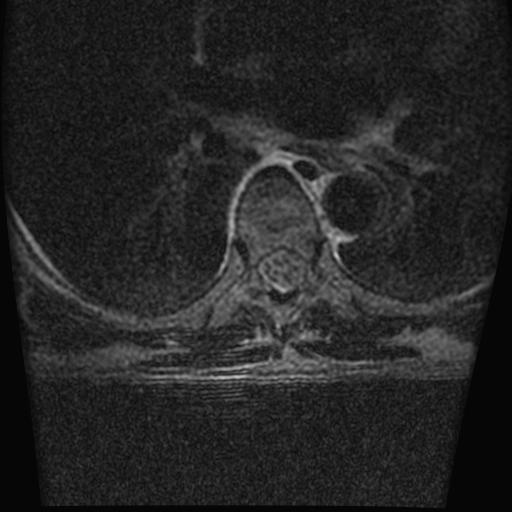

标题: MRI0985:胸椎.68岁男性,胸部疼痛,

68岁男性,胸部疼痛,不适。

胸7椎体楔状变形及信号异常,附件未见明显异常信号.椎间隙正常.未见软组织块影.考虑骨质疏松所致压缩性骨折可能大.

胸7椎体楔状变形及信号异常[t1t2 均为低信号],附件未见明显异常信号.椎间隙正常.未见软组织块影.考虑陈旧性压缩性骨折伴退变。

首先需除外单发成骨性转移瘤可能。